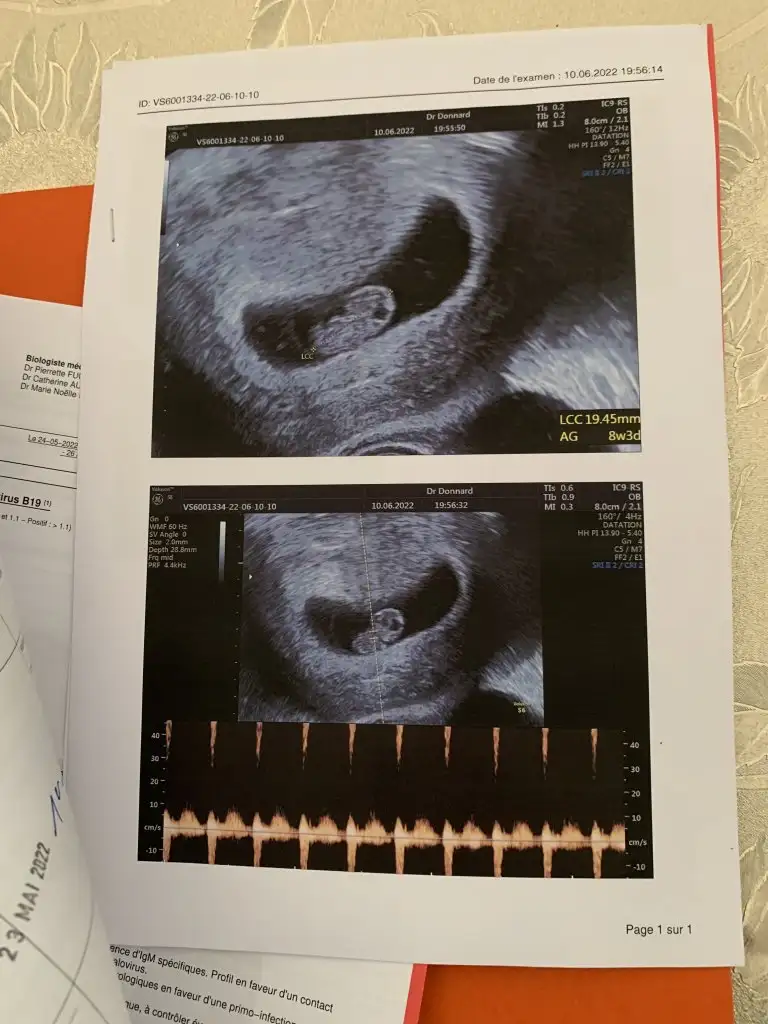

İlk ultrason resmine göre cinsiyet tahmini

Ben birşey merak ediyorum dun doktora ilk defa gittim karından muayenede goremedı alttan muayenede 5 haftalık dedı ama ultrasyonda boyle kesenın ıcınde bırsey yok bombos duruyor adet tarıhıme gore hesaplama yaptı ama ben 5 haftalık oldugunu sanmıyorum

Merhaba canim Benim ilk vajinal ultrasonumu simdi sana yolayacagim Benimde cok az sanki kese yok gibi 4haftaliktim o zamanlar Bende sasirdim nasil 4hafta Ama birsey ki doktorlar son ader tarihinden gebeligi saymaya basliyor ondan çok geliyor bende 4hafta dediginde sasirmistim

Ben konuyla alakasız birsey soracam 5 haftalık ama kesenin icinde birşey yok acaba doktor haftayı mı yanlış soyledı burda bakıyorum 6 haftalıklar da kocaman birşy var kesede benim bomboş gorunuyordu

Geç döllenme olabilir belki ya da kişiden kişiye değişir diye düşünüyorum